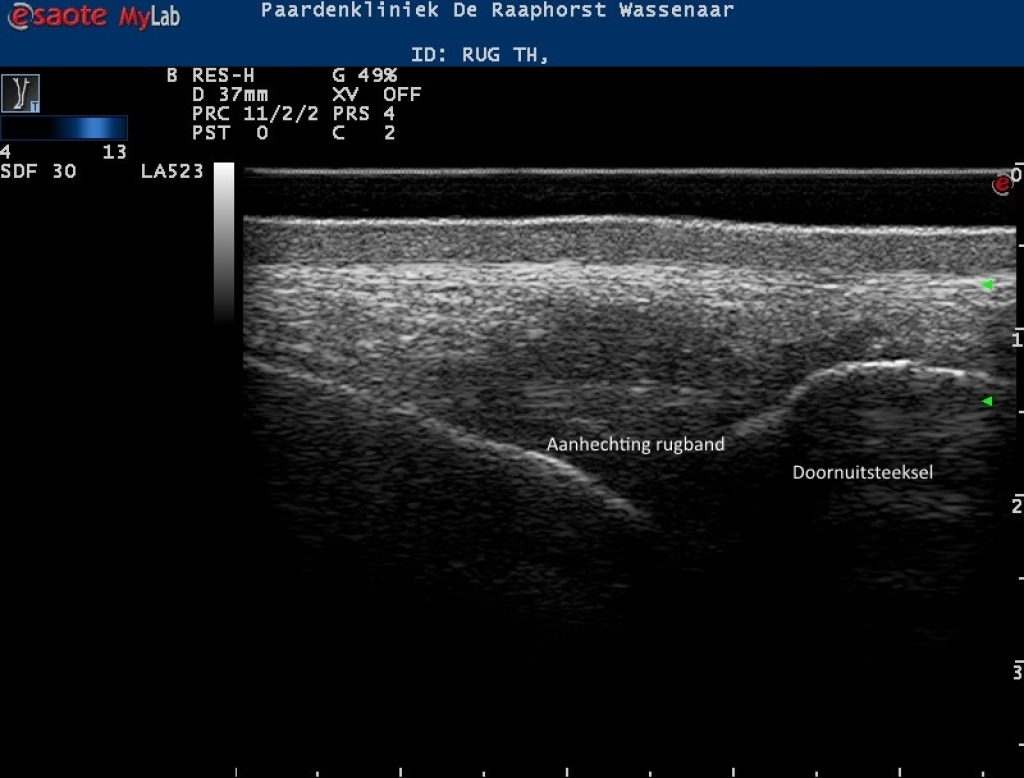

Echobeelden van de lengte en dwarsdoorsnede van de rugband

Foto: Echobeelden van de lengte en dwarsdoorsnede van de rugband